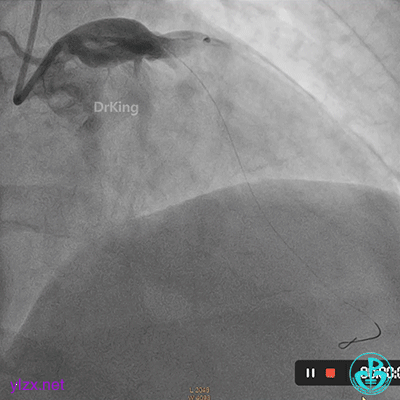

首选开通右冠脉,导丝到达闭塞段远端,球囊扩张后,可见大量血栓,抽吸导管反复抽吸出大量血栓。冠脉内推注尿激酶原20mg,复查造影提示右冠脉远端显影,调整导丝至远段。

球囊再次扩张闭塞段,并对后降支及左室后支开口行对吻球囊扩张,复查造影示血流3级,无夹层行成,右冠脉远段仍可见血栓影。